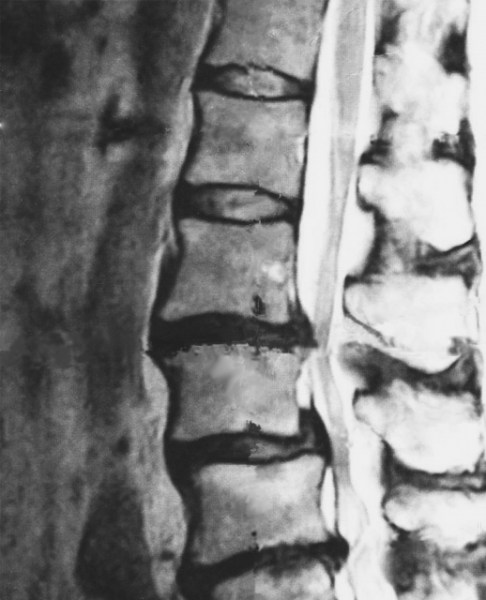

意外にも早く3ヶ月後には通知が届きました。なかみは『該当なし』、つまり棄却という結果です。疑いがあれば、その審議にさらに時間がかかるのでしょうけれど、私の場合は画像でヘルニアの度合いが一目瞭然、痛いのは痛いのだろうけれど、歩行が困難なほどの程度ではなく、異議申立の理由なしということのようです。